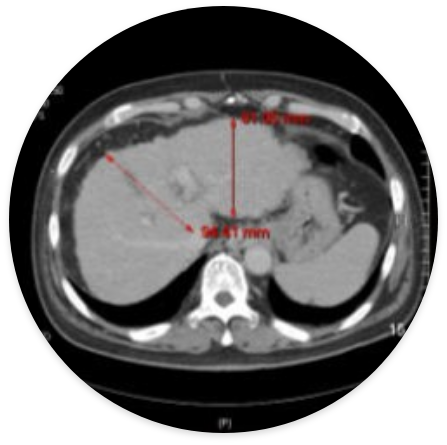

간경변 (59세 남성) – 시술 후 간세포가 재생되어 간의 크기가 증가하고 간 조직이 부드러워짐